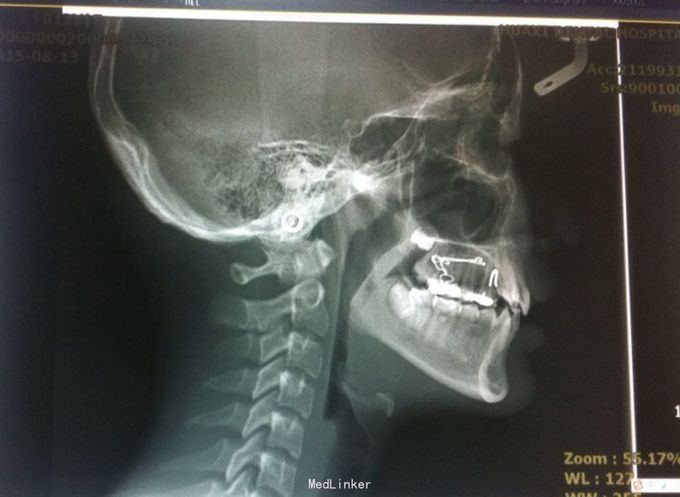

恒牙期 口内见摆式矫治器 左侧磨牙近中关系,右侧中性关系 前牙覆合覆盖正常 中线不正 上下牙列拥挤 张口度正常 关节有弹响 开口型异常

安氏三类 拆除摆式矫治器,清洁牙面,直丝弓矫治器,排齐整平上下牙列,矫治后磨牙中性关系,前牙覆合覆盖正常,维持现有面型

1、在治疗过程中根据面型可能需要片磨上下牙 2、18、28、38、48牙胚存在,必要时拔除